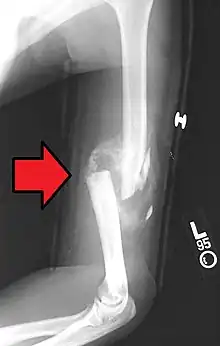

- Non-union: no progression of healing within six months of a fracture occurring. The fracture pieces remain separated and can be caused by infection and/or lack of blood supply (Ischaemia) to the bone.[9] There are two types of non-union, atrophic and hypertrophic. Hypertrophic involves the formation of excess callus leading to bone ends appearing sclerotic causing a radiological "Elephants Foot" appearance[6] due to excessive fracture ends mobility but adequate blood supply.[4] Atrophic non-union results in re-absorption and rounding of bone ends[6] due to inadequate blood supply and excessive mobility of the bone ends.[4]